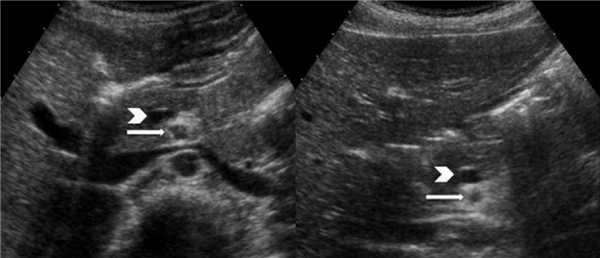

Рисунок. На УЗИ нормальное положение третьего сегмента 12-ти перстной кишки.

Рисунок. Схема местоположения третьего сегмента 12-ти перстной кишки (D3) в норме (справа) и при мальротации кишечника (слева).

При незавершенном повороте брюшинные тяжи натянуты над 12-ти перстной кишкой и могут вызывать дуоденальную обструкцию, тогда желудок и проксимальный отдел 12-ти перстной кишки расширены. На рентгене определяются два газовых пузыря с уровнем жидкости. Полная обструкция характерна для атрезии, тогда газ в нижележащих отделах кишечника отсутствует. При незавершенном повороте чаще встречается неполная обструкция, тогда определяется газ в нижележащих отделах кишечника. На УЗИ после кормления определяют две заполненные жидкостью полости — желудок (звездочка) и проксимальный отдел 12-ти перстной кишки (стрелки).

Рисунок. Новорожденный с подозрением на высокую кишечную непроходимость. На рентгене и на УЗИ знак двойного пузыря. Во время операции определили незавершенный поворот с брюшинным тяжем над 12-ти перстной кишкой.